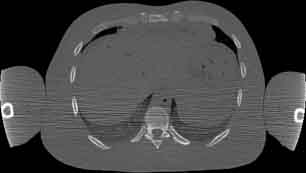

Visible Human male: Sectio transversalis 1495

CT

NMR

Pd                          / T2 \                         T1